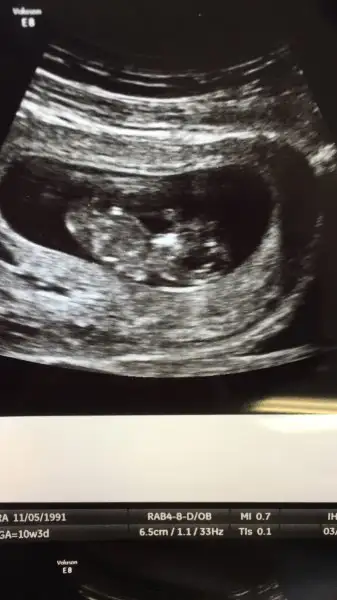

İkili test yaptirdik.kan verdim.kan sonucu 1 ay sonra çikacakmis.

Ense ölcümü de 1.2 çıktı.yani normal dedi

Bebisi de gördüm.dr yaklasik 6 cm dedi.

Hafta olarak 12+3 çikti.